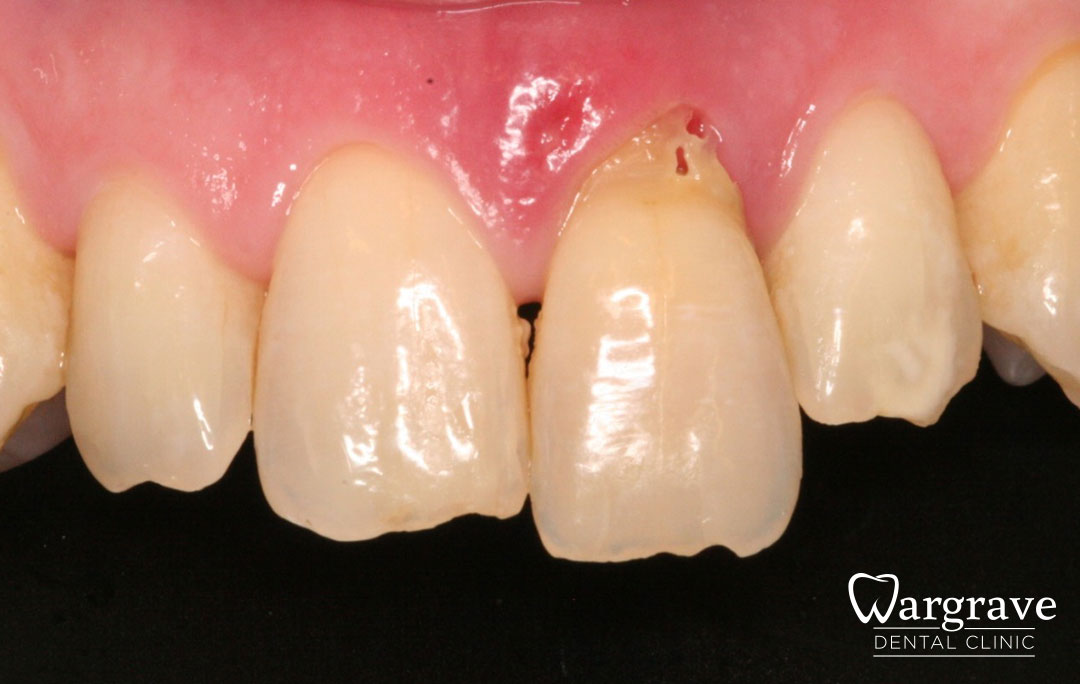

Healthy Smiles These are more advanced examples of different treatments available.All cases shown were carried out by Dr R Khurana unless otherwise stated. Immediate implants Anterior Mandible Bone Regeneration Anterior Mandibular Implant Bridge Maxillary Anterior Implant Bridge Implant stabilised ‘Life Like’ replacement dentures Implant Bridge after 10-years with zero bone loss Implant examples including ZBLC concepts Adhesive Bridge solution for a missing premolar Multidisciplinary care Orthodontics, Replacement veneers and composite bonding Adhesive Bridge solution for missing central incisors Replacement crown, Veneer and Composite Bonding Replacement Crowns and Veneer Injection Moulding using Composite Resin Equilibration Tooth Whitening to treat Developmental Discolouration